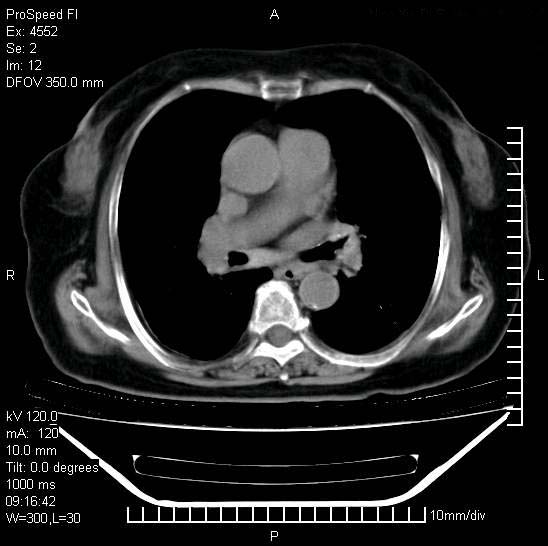

标题: CT15528:女性,79岁,近几日晚上高热,39度,仍咳少量血 [打印本页]

标题: CT15528:女性,79岁,近几日晚上高热,39度,仍咳少量血

十几年前曾患肺结核,一周前突咳血约100ml,中性粒细胞稍高,诊断两上肺陈旧结核,下肺炎症,给予抗炎治疗,近几日晚上高热,39度,仍咳少量血,4天前ct及今天ct上传。

[face=黑体]8月30日[/face]

支持陈旧性肺结核并两下肺感染,两侧胸腔积液。

短短几天内,病变范围明显增多扩大,以左侧明显,而且双侧出现胸水,还是考虑感染.

短短几天内,病变范围明显增多扩大,以左侧明显,而且双侧出现胸水,我更多考虑左侧中心性肺癌并并阻塞性不张及肺炎,炎症变化也太快了!

1)两肺结核并感染。2)不排除左肺上叶中央型肺癌并阻塞性肺炎、肺不张可能;建议行纤支镜检查。3)右肺门及纵隔淋巴结肿大。4)双侧胸腔积液。